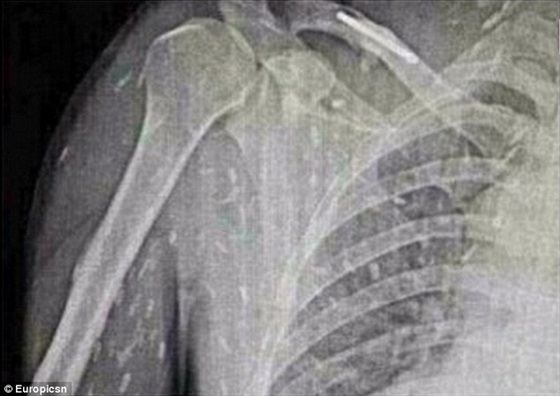

وكان الرجل ذهب إلى الطبيب يشكو من ألم في المعدة وحكة في الجلد، وكشفت الأشعة أن جسمه بالكامل أصيب بعدوى الدودة الشريطية .